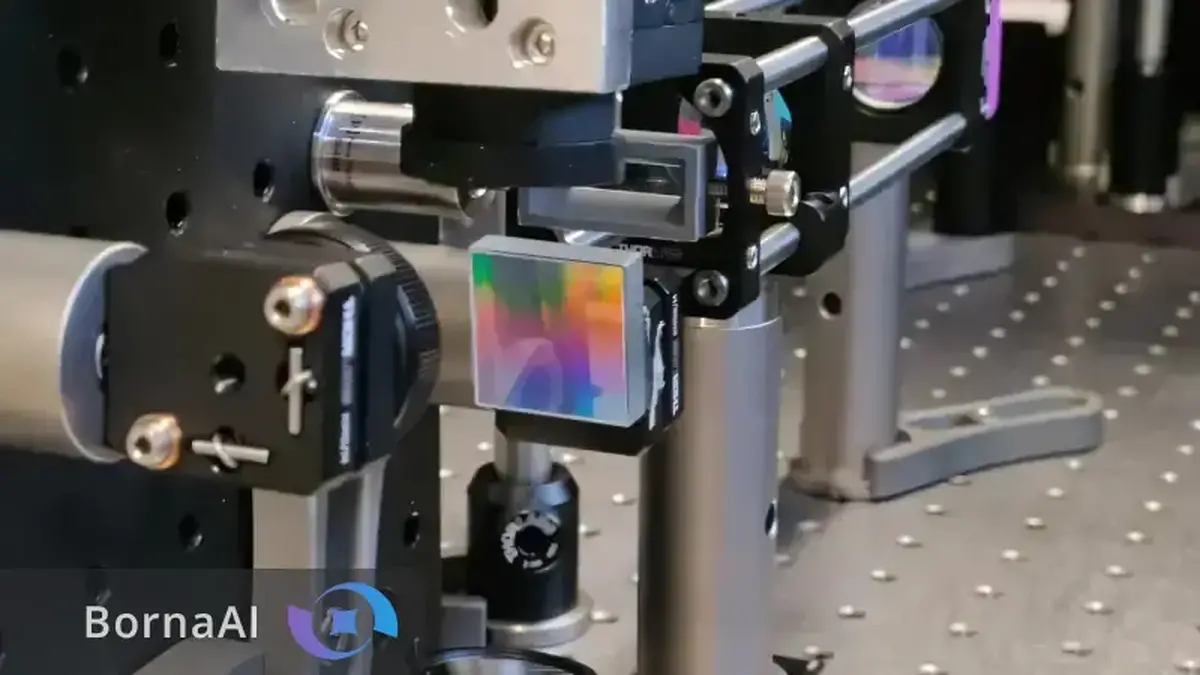

اکنون تیمی پژوهشی به سرپرستی ماریوس جورجیادیس، مدرس تصویربرداری عصبی روشی ساده، مقرونبهصرفه و دقیق برای آشکارسازی این شبکههای پنهان توسعه داده است. این روش که تصویربرداری محاسباتی نور پراکنده (Computational Scattered Light Imaging – ComSLI) نام دارد که در نشریه Nature Communications معرفی شده است.

ComSLI با تکیه بر رفتار فیزیکی ساده نور این محدودیتها را برطرف میکند. هنگامی که نور از ساختارهای میکروسکوپی عبور میکند الگوی پراکندگی آن به جهتگیری این ساختارها وابسته است. با چرخاندن جهت تابش نور و تحلیل تغییرات پراکندگی جهت الیاف در هر پیکسل تصویر مشخص میشود.

این روش تنها به یک منبع نور LED چرخان و دوربین میکروسکوپ نیاز دارد و سپس الگوریتمهای محاسباتی نقشههایی رنگی از توزیع جهت و تراکم الیاف تولید میکنند.